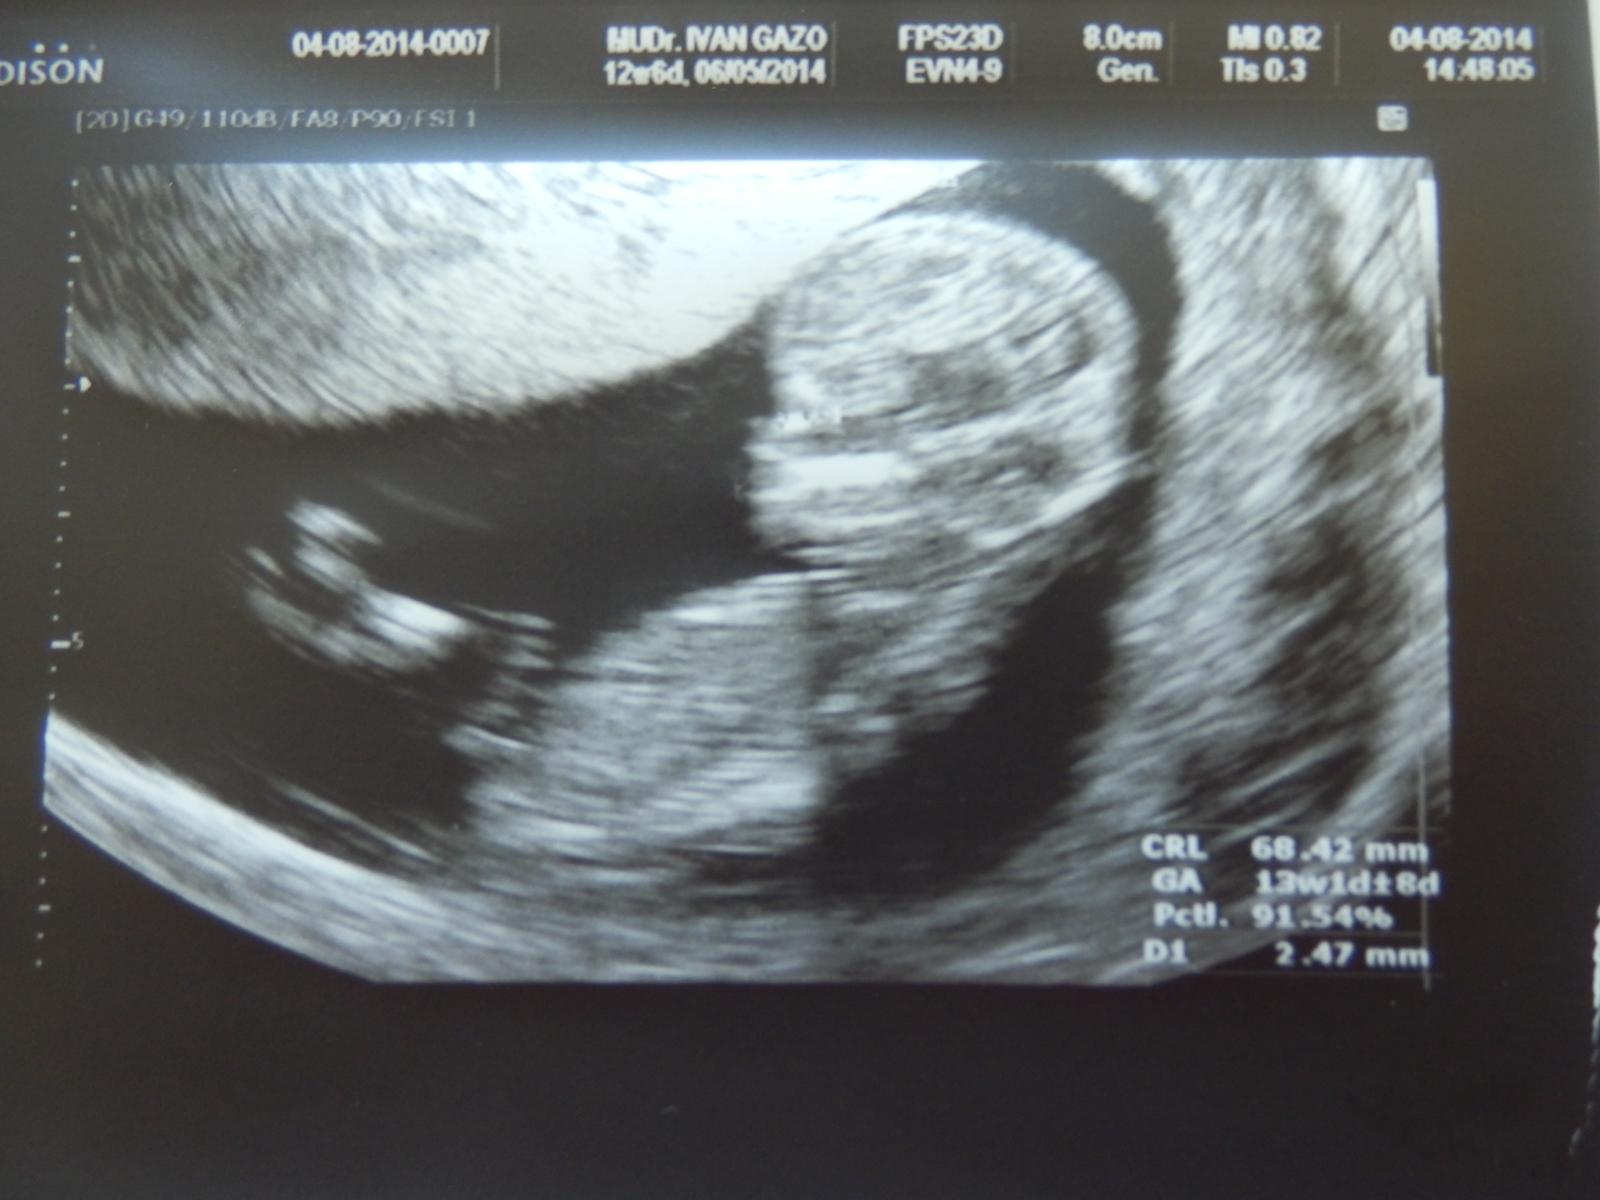

@siska765 ku komu chodis? Ja ku gazovi.